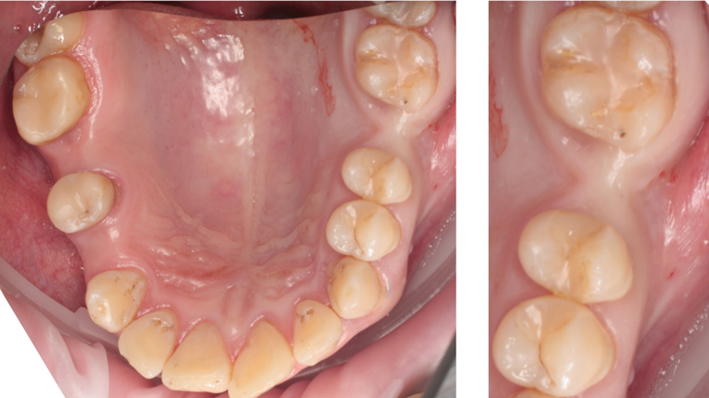

Clinical case: Installation of dental implants in complicated anatomic conditions using crest lifting methods

- Courtesy of Dr.Alexander Lysov, Russia -

Keywords

AnyRidge, complicated anatomic conditions, crest lift, MICA Kit, Dr. Alexander Lysov, bone regeneration, GBR, #26, maxillary posterior

“Thin ridge expansion with minimally invasive surgery!

Use SmarThor & AnyRidge to place a wider diameter implant with minimal drilling after ridge splitting, even in thin ridge under 2mm! “

Clinical case: Ridge splitting technique using SmarThor + AnyRidge as expander

- Courtesy of Dr.Kwang-Bum Park, Korea -